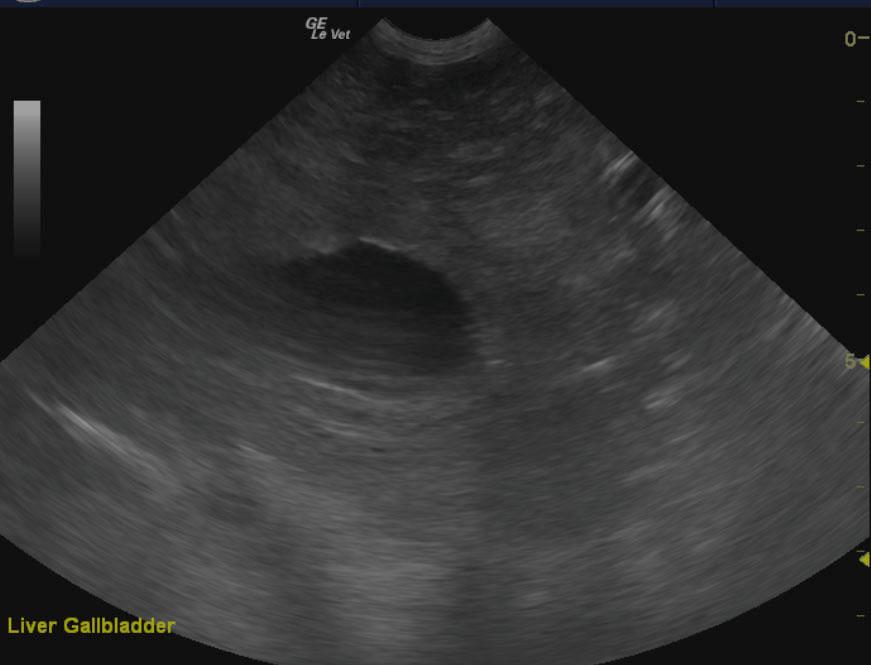

The liver in this patient presented an 8.8 x 7.6 cm, mixed, hyperechoic nodular mass with areas of capsular expansion and reactive surrounding omentum. Microaccumulation of fluid was noted within the mass as well. It appeared to derive from the left liver and extend into the deep left liver enveloping the cranial aspect of the gallbladder and separate nodular changes were noted in the right liver in the region from the vena cava inlet through the diaphragm. Loss of architecture was noted throughout this region. The gallbladder revealed a minor amount of dependent debris. The mass appeared to impinge upon the portal vein from the left side with nodular changes on the right side are suspected as well.